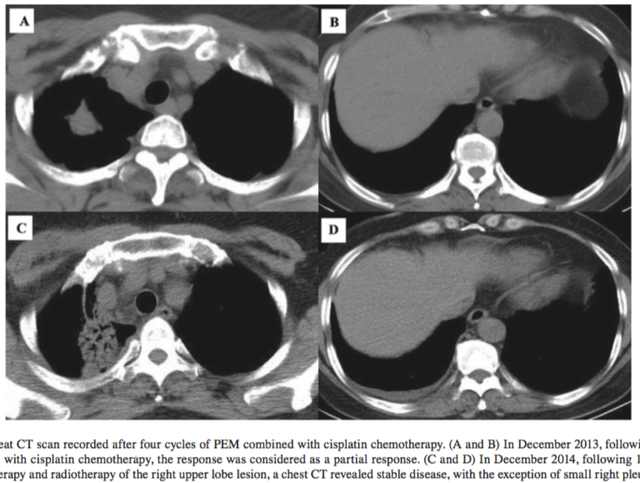

患者一线选择化疗,方案为培美曲塞(500mg/m2)联合顺铂(75mg/m2),每3个星期一个疗程。四个疗程之后评估为PR,患者对化疗部分应答,肿瘤病灶缩小。由于一线化疗结果不错,患者单药培美曲塞(500mg/m2)维持治疗了12个疗程,病情显示稳定。然后患者还接受了放射治疗。放疗之后继续培美曲塞单药维持治疗。

2015年3月,距离一线化疗之后的18个月,患者主诉右胸疼痛不适,CT影像学显示肿瘤复发。